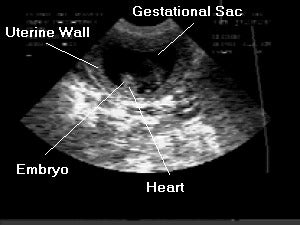

- Pregnancy: The uterus can be scanned to diagnose pregnancy, determine the age of the fetuses, and monitor fetal development and viability.

We can see the ribs (the white structure in the middle causing shadowing because ultrasound waves do not go through bone), the developing heart and lungs of the fetus.

Ultrasound pregnancy confirmation is possible as early as day 20-22, but can be missed this early. Ultrasound at day 30 post- mating is a great diagnostic tool to confirm pregnancy. Ultrasound has the drawback of not being accurate to count puppies, but can determine heartbeats in the puppies.